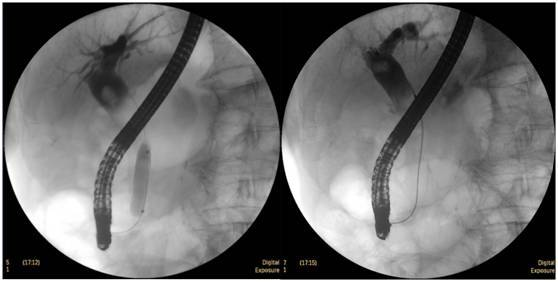

搭配DRCF的ERCP診斷優勢:

膽囊結石

ERCP膽囊顯影,見多枚結石影。

鼻膽管造影

立位注入造影劑,膽總管顯影好,稍擴張,未見結石影。

膽總管結石

柱狀球囊擴張完全,膽總管擴張,下段見充盈缺損影。

膽總管擴張,下段見明顯充盈缺損(上圖為反片且局部放大后效果)

柱狀球囊擴張膽總管下段及乳頭(上圖為使用取石網籃取石)。